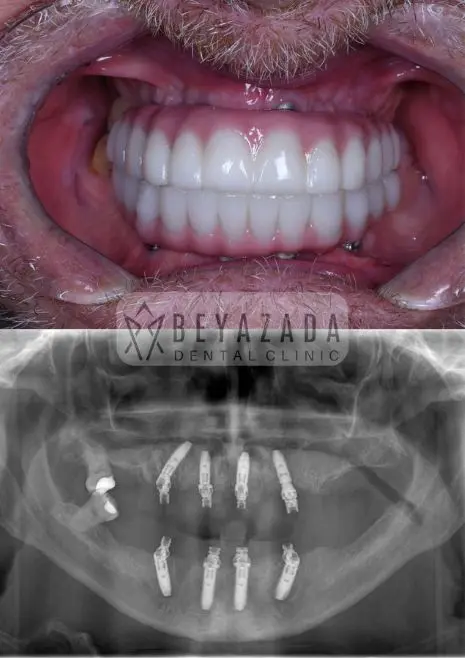

Smile Gallery

At Beyazada Dental Clinic, we take pride in the visible and emotional transformations our patients experience through All-on-Four treatment. Our case studies highlight real individuals from across Europe who arrived with serious dental challenges and left with life-changing smiles.

Before-and-after photo comparisons demonstrate dramatic improvements in facial harmony, tooth alignment, and bite functionality. These visuals showcase not only aesthetic enhancements but also restored self-esteem and quality of life.